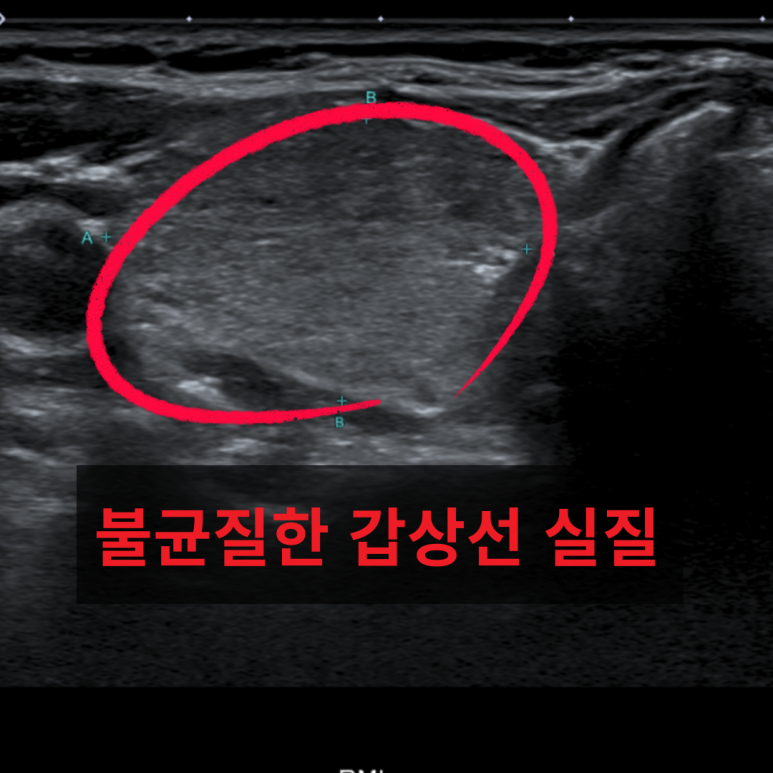

• 갑상선 초음파: 불균질 갑상선 실질 갑상선 초음파: 불균질 갑상선 실질

TSH 0.01, Free T4 3.69↑, TSI 6.57↑, 초음파 검사 결과 갑상선 비대·불균질 실질 발견→ 그레이브스병 진단. 약물치료 후 수치 호전.

혈액검사에서 TSH 수치 감소, Free T4 3.69 ng/dL, TSI 6.57그레이브스병에 의한 갑상선기능항진증을 확진했습니다. 초음파에서는 양측 갑상선 비대·불균질 실질이 확인되었습니다. 약물치료 시작 2주 후 증상 호전, 추적 검사에서 Free T4 1.09로 호전되었습니다.